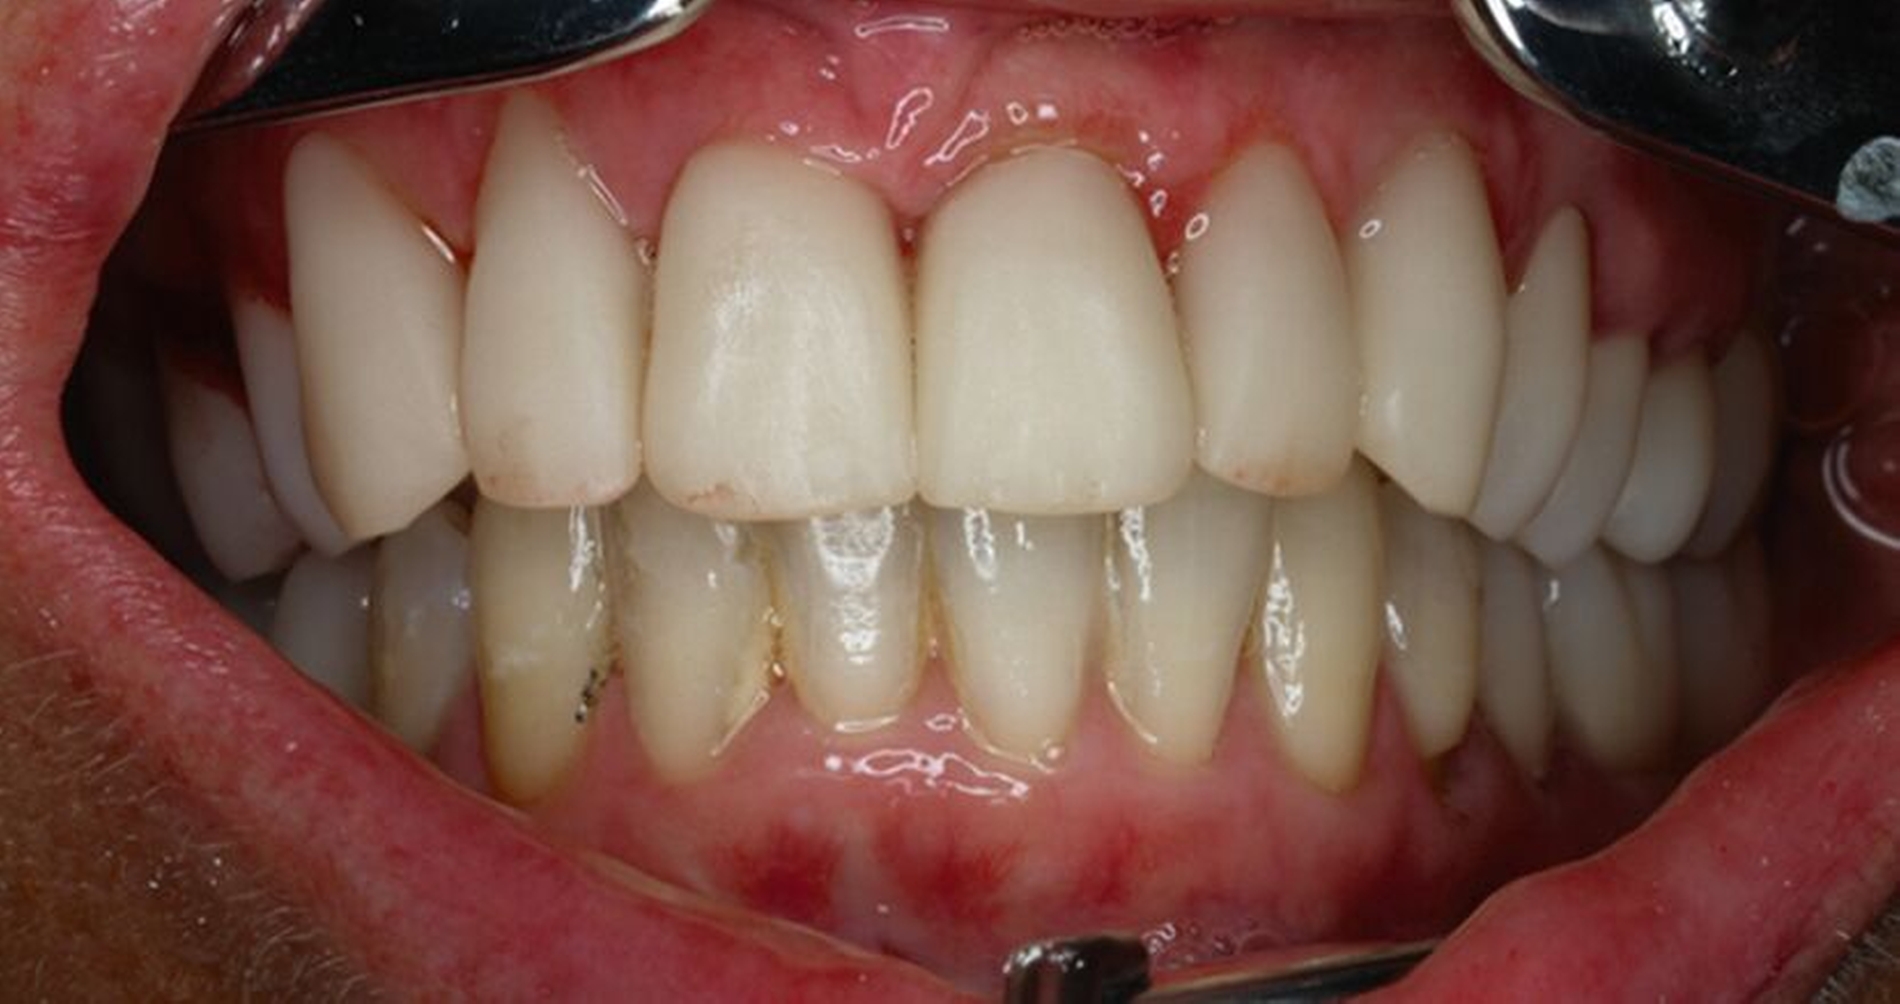

Klinisch zeigten sich diverse großflächig, mehrheitlich mit Amalgam gefüllte Seitenzähne, suffiziente endodontische Behandlungen an den Zähnen 16 und 14 sowie intakte Kronen an den Zähnen 16 und 48 (Abbildung 2). Ein Parodontaler Screening-Index (PSI) wurde erhoben (1-1-0-0-2-1), der stabile Verhältnisse nachwies. Das funktionelle CMD-Screening zeigte eine nicht-druckdolente Kaumuskulatur sowie eine uneingeschränkte Mundöffnung ohne Reiben und Knacken.

Tabelle 1 zeigt das entsprechende Befundschema mit den Taschentiefen mesial und distal, den Lockerungsgraden und den Sensibilitätsüberprüfungen mittels Kältespray (ViPr). Die Ruheschwebelage wurde mithilfe des Zielinsky-Zirkels auf 2 mm bestimmt. Die Nonokklusion im Seitenzahnbereich konnte auf circa 1,5 mm bemessen werden. Tabelle 2 spiegelt das entsprechende Okklusionsprotokoll wider. Das Okklusionsprofil wird auch in den Abbildungen 3a bis 3c deutlich.

Die anschließenden Verlaufskontrollen zeigten klinisch stabile Verhältnisse. Der prothetische Behandlungsaufwand betrug etwa acht Monate inklusive Planung, Begutachtung, Durchführung und Inkorporation des Zahnersatzes. In den Folgeterminen wurde der Patientin noch eine Aufbissschiene für den Unterkiefer eingegliedert, um Schäden durch etwaigen Schlafbruxismus vorzubeugen [Macedo et al., 2007]. Für die Nachsorge empfiehlt sich ein halbjährliches Kontrollintervall. Die erfolgte Okklusionskorrektur im Seitenzahnbereich wird in Abbildung 11 deutlich.